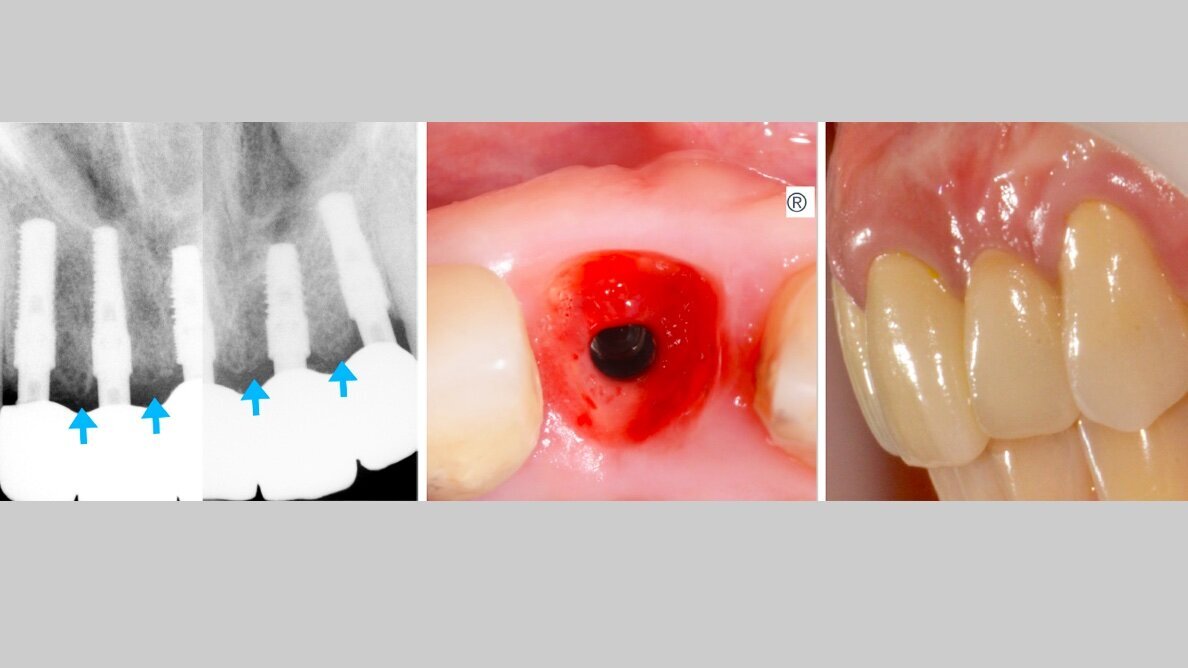

Imagen 1. Situación clínica previa al tratamiento.

Imagen 4. Emergencias obtenidas con los dispositivos Esculgar.

Imagen 5. Resultado final del tratamiento.

Imagen 6. Radiografías finales del tratamiento con procedimiento de regeneración ósea. Se pueden observar las crestas óseas entre implantes.

En las imágenes se observa el volumen, la regeneración y mantenimiento de las tablas vestibulares de todas las piezas intervenidas, responsables del aspecto de la guirnalda gingival. Sin reabsorción ósea, resultando un tratamiento biológico. “En todo el tratamiento no existe ninguna maniobra clínica, ni del sistema que genere una reacción de defensa que se manifieste como reabsorción, consiguiendo así una integración implanto quirúrgico protético ideal.

Caso donde se observa el volumen, la regeneración y mantenimiento de las tablas vestibulares sin reabsorción ósea, resultando un tratamiento biológico.